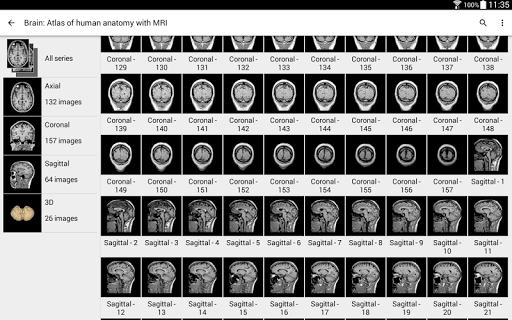

* تحسين عرض التفاصيل للأجزاء التشريحية لتسهيل التعرف عليها في صور الوحدات الحالية والوحدات الأخرى.

- يتذكر التطبيق الآن الفهرس الأخير لكل وحدة حتى تتمكن من الاستئناف إذا تركت بشكل أسرع

انقر أيضًا مباشرة على الصورة للانتقال إلى الصورة المعروضة في تلك الوحدة